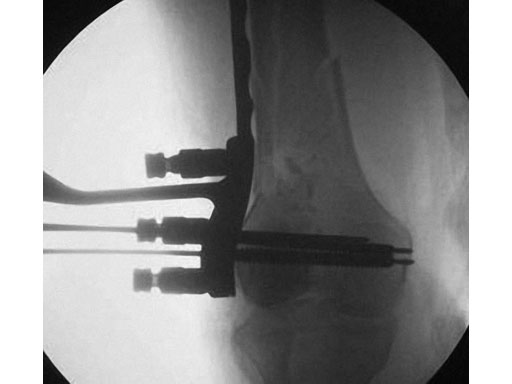

The LCP periarticular aiming instruments are indicated to facilitate percutaneous, submuscular insertion of the LCP condylar 4.5 and LCP proximal tibia 4.5.

The set consists of specific aiming arms and handles designed to percutaneously aim for screw holes of these plates as well as common instruments such as drill sleeves, drill bits, guide wires, and connection parts.

The aiming arms will allow for percutaneous aiming of the LCP proximal tibia plate 4.5 up to 14 holes and the LCP condylar plate 4.5 up to 18 holes straight or curved.

The new aiming instruments feature several changes compared to the previous generation with the ultimate goal to improve handling. The aiming arms have been changed from PEEK to carbon fibre. The connection points have been redesigned to ensure there is no play or loosening in the aiming arm connection with the handle and plate. Snap-in sleeves through the aiming arms eliminate the use of thumb screws. The instrument color coding and labeling has been made more userfriendly.